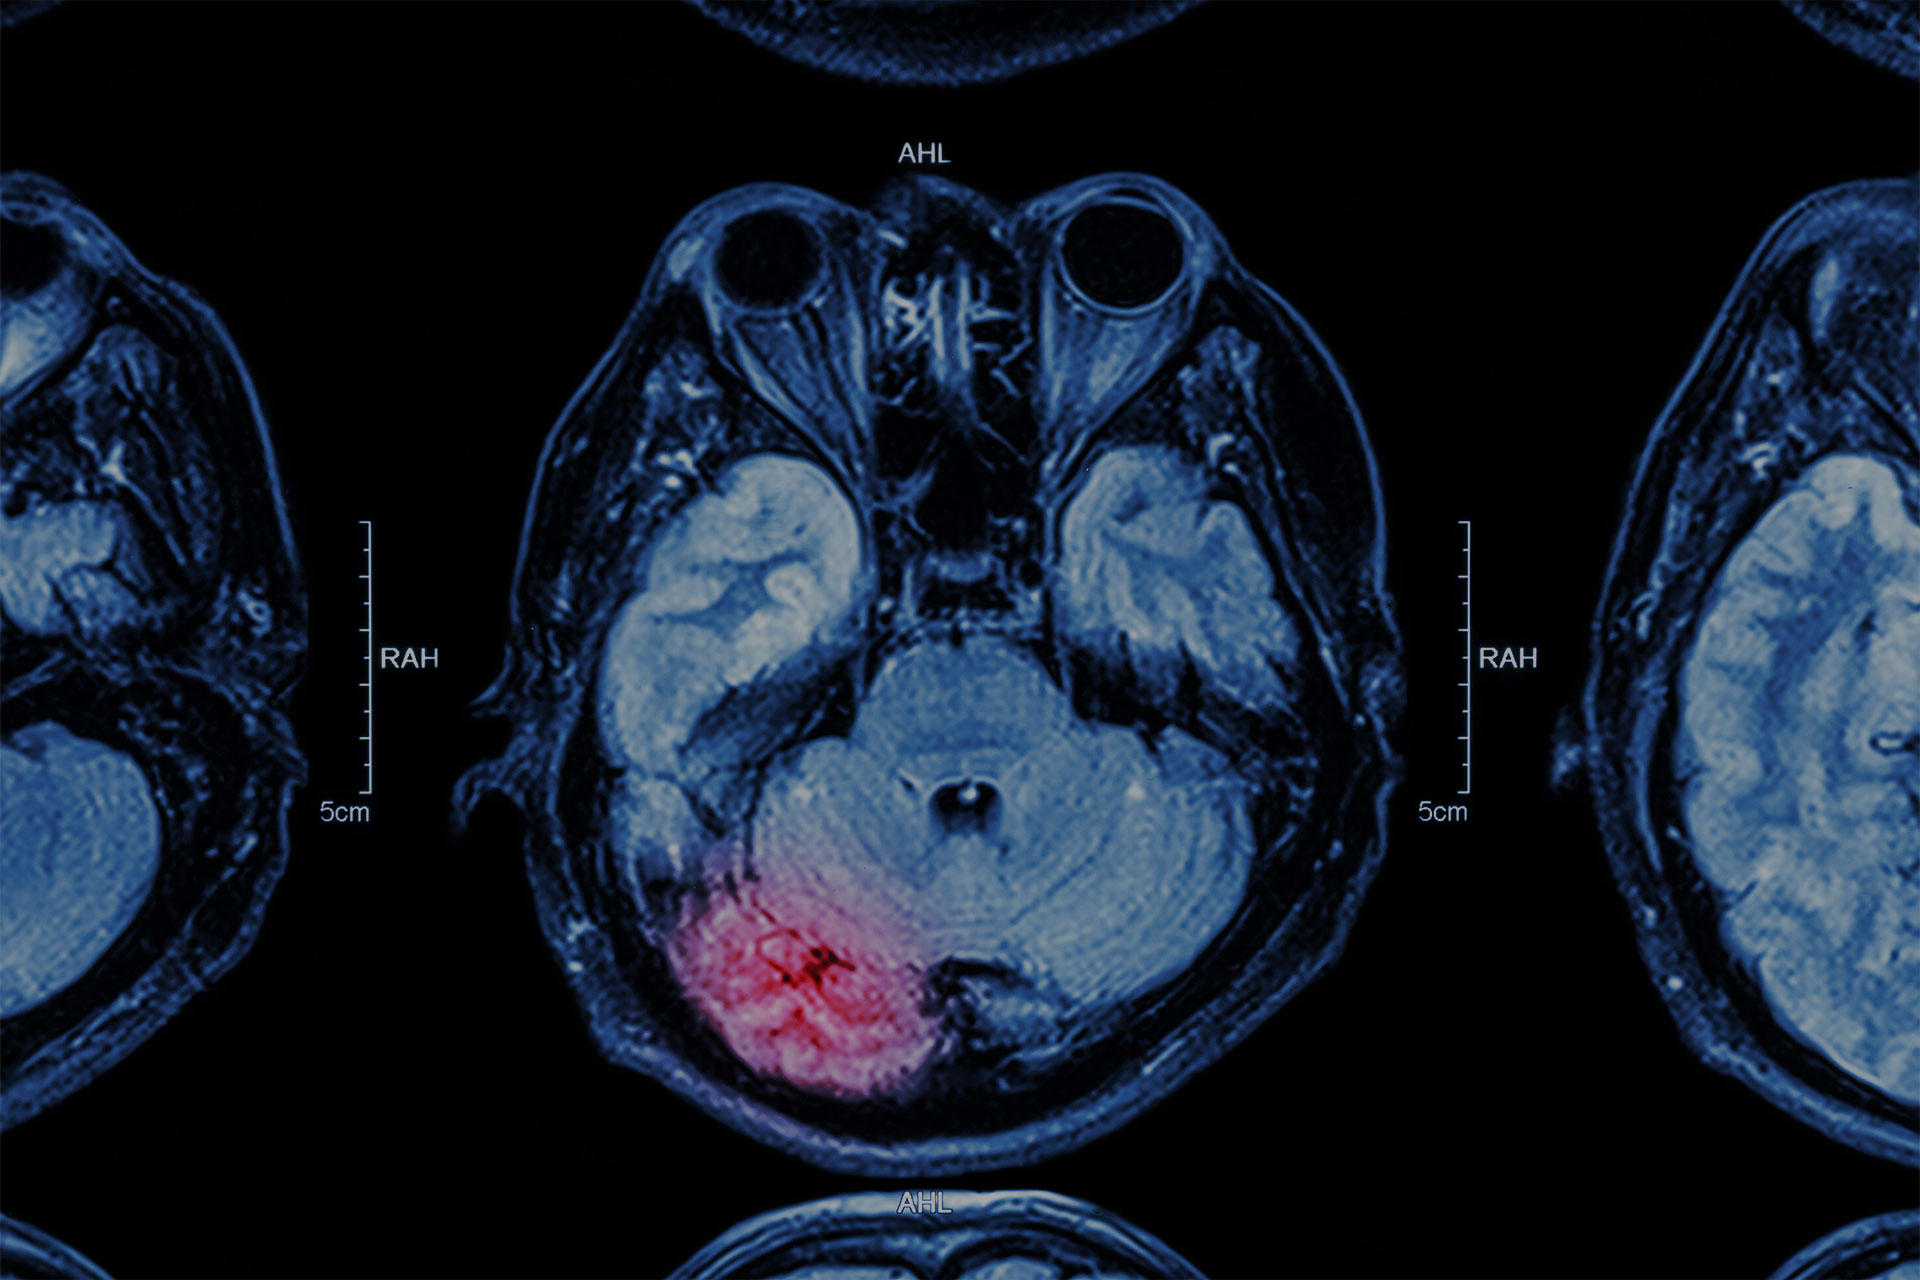

The nervous system is the body’s central command center. The organs in charge of this system are the brain, spinal cord, nerves, and ganglia. All their organs are made of various tissues, including nerve, blood, and connective tissue. The brain controls all of your movements, thoughts, instinctive responses to the world around you, and every system and process, such as digestion, breathing, thinking, and puberty. Neurological diseases, conditions, accidents, trauma, the use of toxins, and the natural aging process can damage your nervous system acutely or chronically.

- Seizure Disorder: A seizure is a sudden, uncontrolled electrical interference between neurons in the brain. It can cause temporary abnormalities in your behavior, movements, feelings, and levels of consciousness.

- Alzheimer’s, including Dementia: Alzheimer's disease is a progressive neurological condition that affects brain size, causing it to shrink and brain cells to die. Alzheimer’s disease is the most common cause of dementia.

- Paralysis: A loss of voluntary muscle function due to strokes or spinal cord injuries. Paralysis affects the function of a specific or widespread part of the body.

- Transient Ischemic Attack (TIA): A Transient Ischemic Attack (TIA), often called a ministroke, is a temporary period of symptoms similar to those of a stroke. A TIA usually lasts only a few minutes and doesn't cause permanent damage to the nerve functions and system.

- We also treat other conditions like Parkinson’s Disease, Cerebrovascular Accident (CVA), Traumatic Brain Injury, and Paraplegia